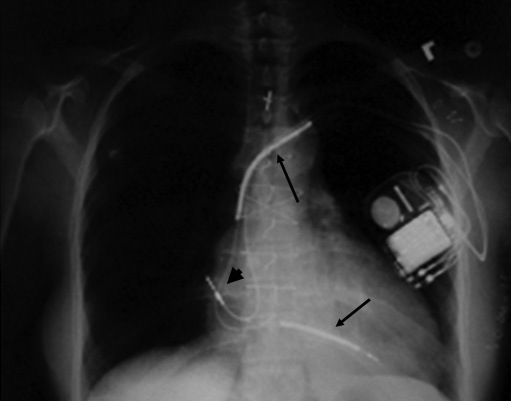

En la Figura 6 se muestra la radiografía de tórax de un paciente con CDI. La gran mayoría de los pacientes requieren una programación del CDI para diagnosticar y tratar una TV y una FV. Así, generalmente el dispositivo se programa con una zona para diagnosticar TV (por lo general frecuencia ventricular entre 150 y 200/min), y otra para FV (habitualmente frecuencia ventricular de 200/min o más). Para tratar la TV el CDI puede aplicar pulsos de estimulación ventricular en varias secuencias y ciclos que son programables, y si luego de varios intentos la arritmia persiste, aplica varias secuencias de shock de baja energía (usualmente 2 a 10 J) hasta lograr convertir la taquicardia (Figura 7). Si la detección de la taquicardia corresponde a una FV, la que puede iniciarse como tal o ser producto de una TV que espontáneamente degenera en FV, o ser consecuencia de alguna de las terapias para convertir una TV (las que en vez de convertirla la degeneran en FV), el CDI aplica una descarga de alta energía (15 a 35 J según lo programado por el electrofisiólogo, la que se repite en forma consecutiva hasta 6 veces por evento, luego de lo cual el dispositivo asume que el paciente no es recuperable. Luego de las terapias para convertir una TV o FV alrededor de un 20% de los pacientes presentan bradiarritmias transitorias, lo que es resuelto con la función de MP que posee el dispositivo.

Figura 6 Radiografía de tórax de un paciente portador de un cardiodesfibrilador implantable.